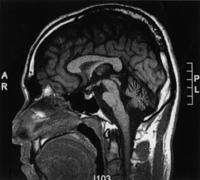

55歳の男性。3年前からろれつが回らず歩行が不安定で介助が必要であり、起き上がるとめまいが起こる。上肢の測定障害のためADLが制限されている。頭部MRIを示す。この患者に対する適切な治療計画はどれか。